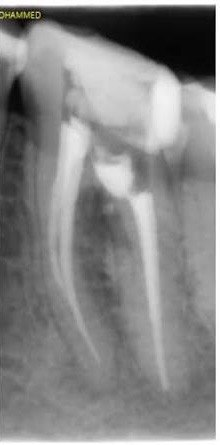

3. What Condition can be seen in this X ray regarding the tooth # 2.2?